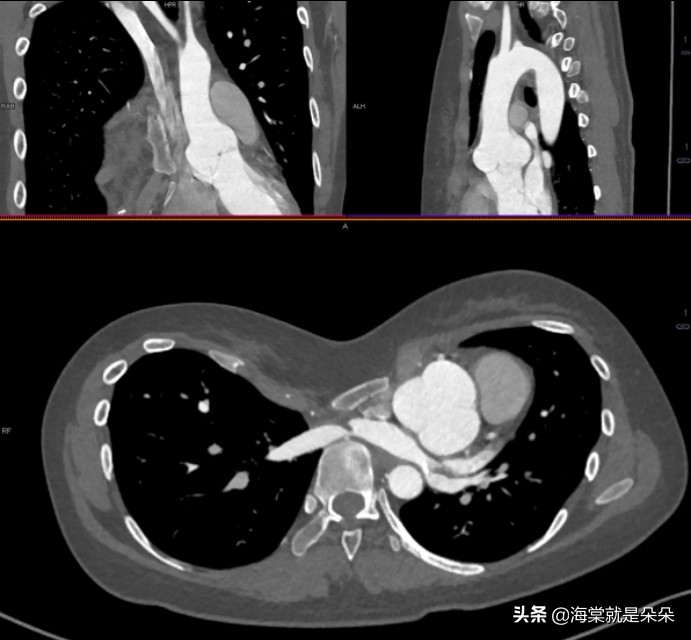

这个女孩20岁才来就诊,Haller指数达到了16!胸骨体都快贴到胸椎了!心脏大血管受压迫移到左边,主动脉窦膨大!

她是体检超声怀疑主动脉瘤的,吓哭了。但是这个漏斗胸确实已经发展到影响器官发育和功能了。需要做手术。